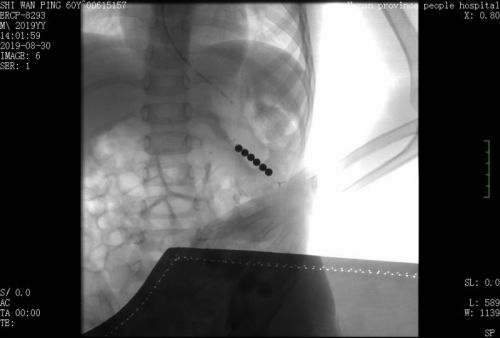

用4颗磁力珠作“钓饵”,将漏网的2颗珠子吸出体外。

此时,难题摆在医生面前,如果不及时取出这两颗珠子,孩子的胃将被磁力吸穿;如果采用外科手术取出,孩子这么小就要遭受开刀之苦,实在不忍心。杨瑜明教授考虑再三,征得家长同意后,决定利用磁力珠的磁性将珠子“钓”出来。他用手套剪了一个指套,在指套内放入4颗磁力珠系在软管上作为“钓饵”,用胃镜将“钓饵”送至贲门处,嵌入粘膜下组织的2颗磁珠被指套内的磁珠吸引,被拖出体外。复查X片发现,小猛体内没有残余金属碎屑,也没有胃穿孔等并发症,“钓鱼”成功!